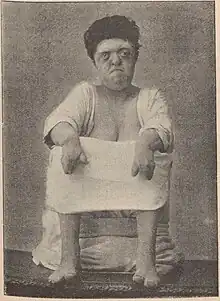

Pansynostosis can present in several ways. The appearance can be the same as that seen with primary microcephaly: a markedly small head, but with normal proportions.[17] The most severe form of pansynostosis is kleeblattschädel (cloverleaf skull), which presents with bulging of the different bones of the cranial vault.[17][18]

Kleeblattschädel is a feature of several conditions and can also be seen in nonsyndromic manifestations. True pansynostosis can also be nonsyndromic[19] but is also seen in two conditions: ERF-related craniosynostosis and Robinow-Sorauf syndrome (now considered a form of Saethre-Chotzen syndrome).[20]